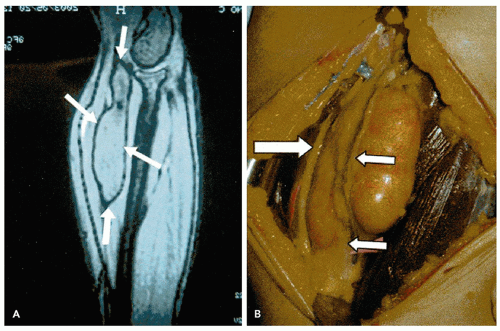

![]() FIGURE 6.4.2 Computed tomography (A) and surgical (B) images of intramuscular lipoma. White arrows highlight the borders of the lipoma within the muscle. |

dome- or egg-shaped and typically measure 2 to 10 cm in diameter. They most commonly appear on the shoulders, neck, trunk, and arms, although they may appear in any part of the body that possesses fatty tissue (Figure 6.4.1). Angiolipomas differ in that they may be painful or tender. Lipomas are usually superficial but may be deep but are not attached to underlying structures (Table 6.4.1). Lipomas may be intramuscular. When present inside an organ, such as muscle, the mass will be difficult to palpate and should be examined by computerized tomography (CT) and/or magnetic resonance imaging (MRI) (Figure 6.4.2). Lipomas have been